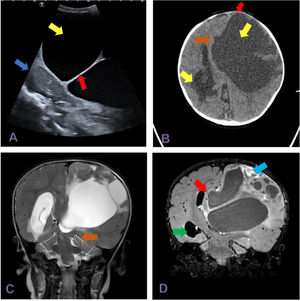

En la ecografía transfontanelar se objetivó una lesión voluminosa anecogénica multiseptada, que provocaba desplazamiento contralateral de la línea media (fig. 1A). Se decidió completar estudio con TC y RM craneal (fig. 1 B-D). En ellas se apreció una lesión hipodensa multitabicada frontoparietal izquierda, que ejercía un efecto de masa sobre el ventrículo lateral izquierdo, provocaba el desplazamiento de la línea media y obliteración de cisternas perimesencefálicas y supraselares con signos de herniación subfalcina y transtentorial descendente.

A) Ecografía transfontanelar con sonda microconvex 5-8MHz (corte sagital) que muestra lesión anecogénica (flecha amarilla), tabicada (flecha roja), de aspecto quístico que comprime el parénquima cerebeloso adyacente (flecha azul). B) TC en corte axial, muestra lesión multitabicada supratentorial con gran componente quístico (flecha amarilla). Ejerce efecto de masa sobre la sutura metópica, que se muestra abombada (flecha roja) con desplazamiento de la línea media (flecha marrón) y dilatación del asta temporooccipital del ventrículo lateral derecho (flecha verde) con edema transependimario por hidrocefalia. C) RM en corte coronal del tronco encefálico en secuencia T2, que muestra herniación transectorial descendente (flecha marrón). D) RM en corte coronal del tronco encefálico en secuencia FLAIR con gadolinio, que muestra gran lesión quística con componente sólido periférico hipercaptante (flecha azul), desplazamiento de la línea media (flecha marrón) y dilatación ventricular con edema transependimario (flecha verde).

El paciente fue intervenido con resultado anatomopatológico de ganglioglioma desmoplásico infantil.